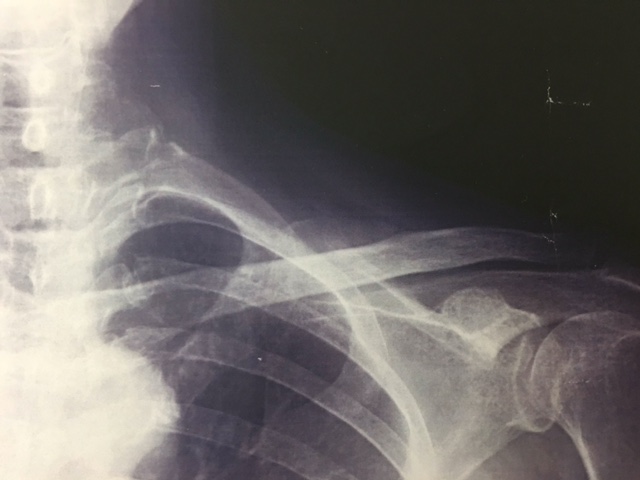

さて、今回は『鎖骨骨折』について、紹介させていただきます。

それは鎖骨の形状にあります。鎖骨はS状の骨でありその曲がっているところに力が集中してしまうからです。そのため骨の丈夫な方でも骨折してしまうのです。

一般的には、大きな衝撃により起こるといわれ、スポーツや運動中の転倒で起きやすいです。また、骨粗しょう症などで骨がもろくなってしまっている場合には、軽い転倒でも骨折してしまいます。

鎖骨骨折はずれを生じることがほとんどであるため、適切な処置を行わなくてはいけません。自己判断でそのままにしていると、手にシビレが出たり、手が挙がらなかったりと後遺症が残ってしまいます。